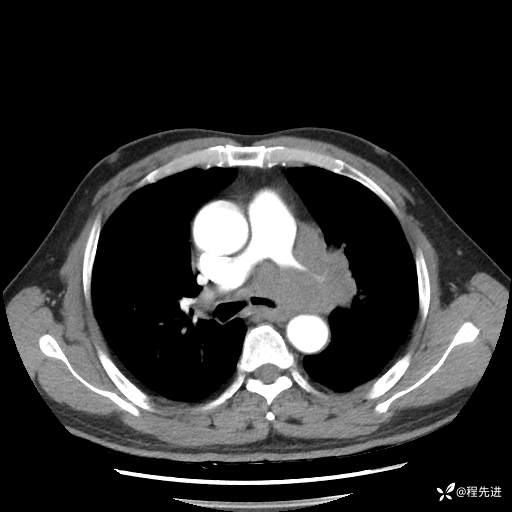

患者性别:男

患者年龄:57岁

简要病史:声嘶2月余

CT平扫+增强: